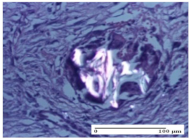

| AL group | ![]() | ![]() | ![]() |

| normal striated muscle, Score 1 | granulation tissue in course of conjunctive organization, Score 1 | normal hair, detail in polarized light microscopy, Score 0 | |